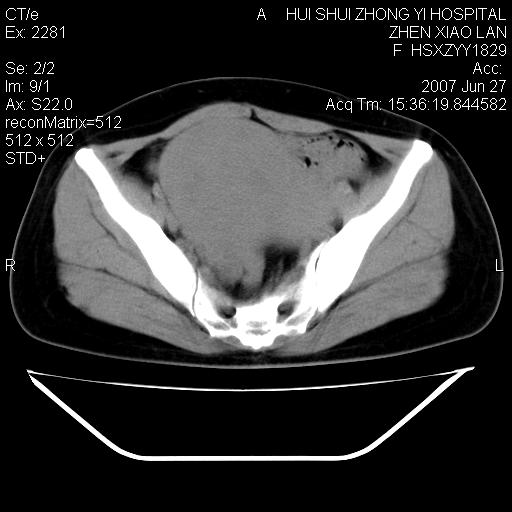

以下是引用还珠格格在2007-6-28 15:15:00的发言:[br]子宫明显增大,偏向盆腔右侧,密度均匀,和子宫同密度, 考虑 子宫肌瘤可能性大 建议增强 除外子宫平滑肌肉瘤。

以下是引用dyqct在2007-6-28 15:41:00的发言:[br]考虑多发子宫肌瘤可能性大,建议进一步增强检查。